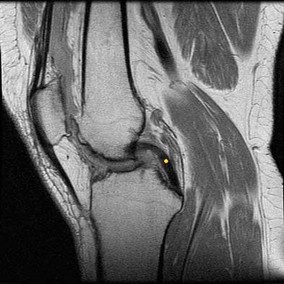

CLINICAL SITUATION FOR QUESTIONS 22 THROUGH 25

A 22-year-old man sustains an injury to his right knee in a motor vehicle collision. Figure 22a is the posterior stress radiograph of the involved knee, and Figure 22b is a selected MR image that identifies the injured structure.

Which relationship is noted for the structure identified by the arrow in Figure 22b? 24

- The anterolateral bundle is tensioned in mid flexion, and the posteromedial bundle is tensioned in both extension and high flexion.

The stress radiographs demonstrate posterior instability of the right knee in flexion. The MR images demonstrate injury to both the anterior and posterior cruciate ligament (PCL), with the stump identified with the arrow on the MR image (Figure 22b). The PCL has 2 functional bands. The anterolateral bundle originates from the roof of the intercondylar notch. It runs in a posterolateral direction onto the tibial crest between the posterior attachment of the medial and lateral menisci. During a double-bundled posterior ligament reconstruction, the

anterolateral bundle is tensioned with the knee in a position of mid flexion. The posteromedial bundle has a variable pattern of tension both in extension and in high flexion. Tensioning of the posteromedial bundle in extension may contribute to resistance against knee hyperextension.